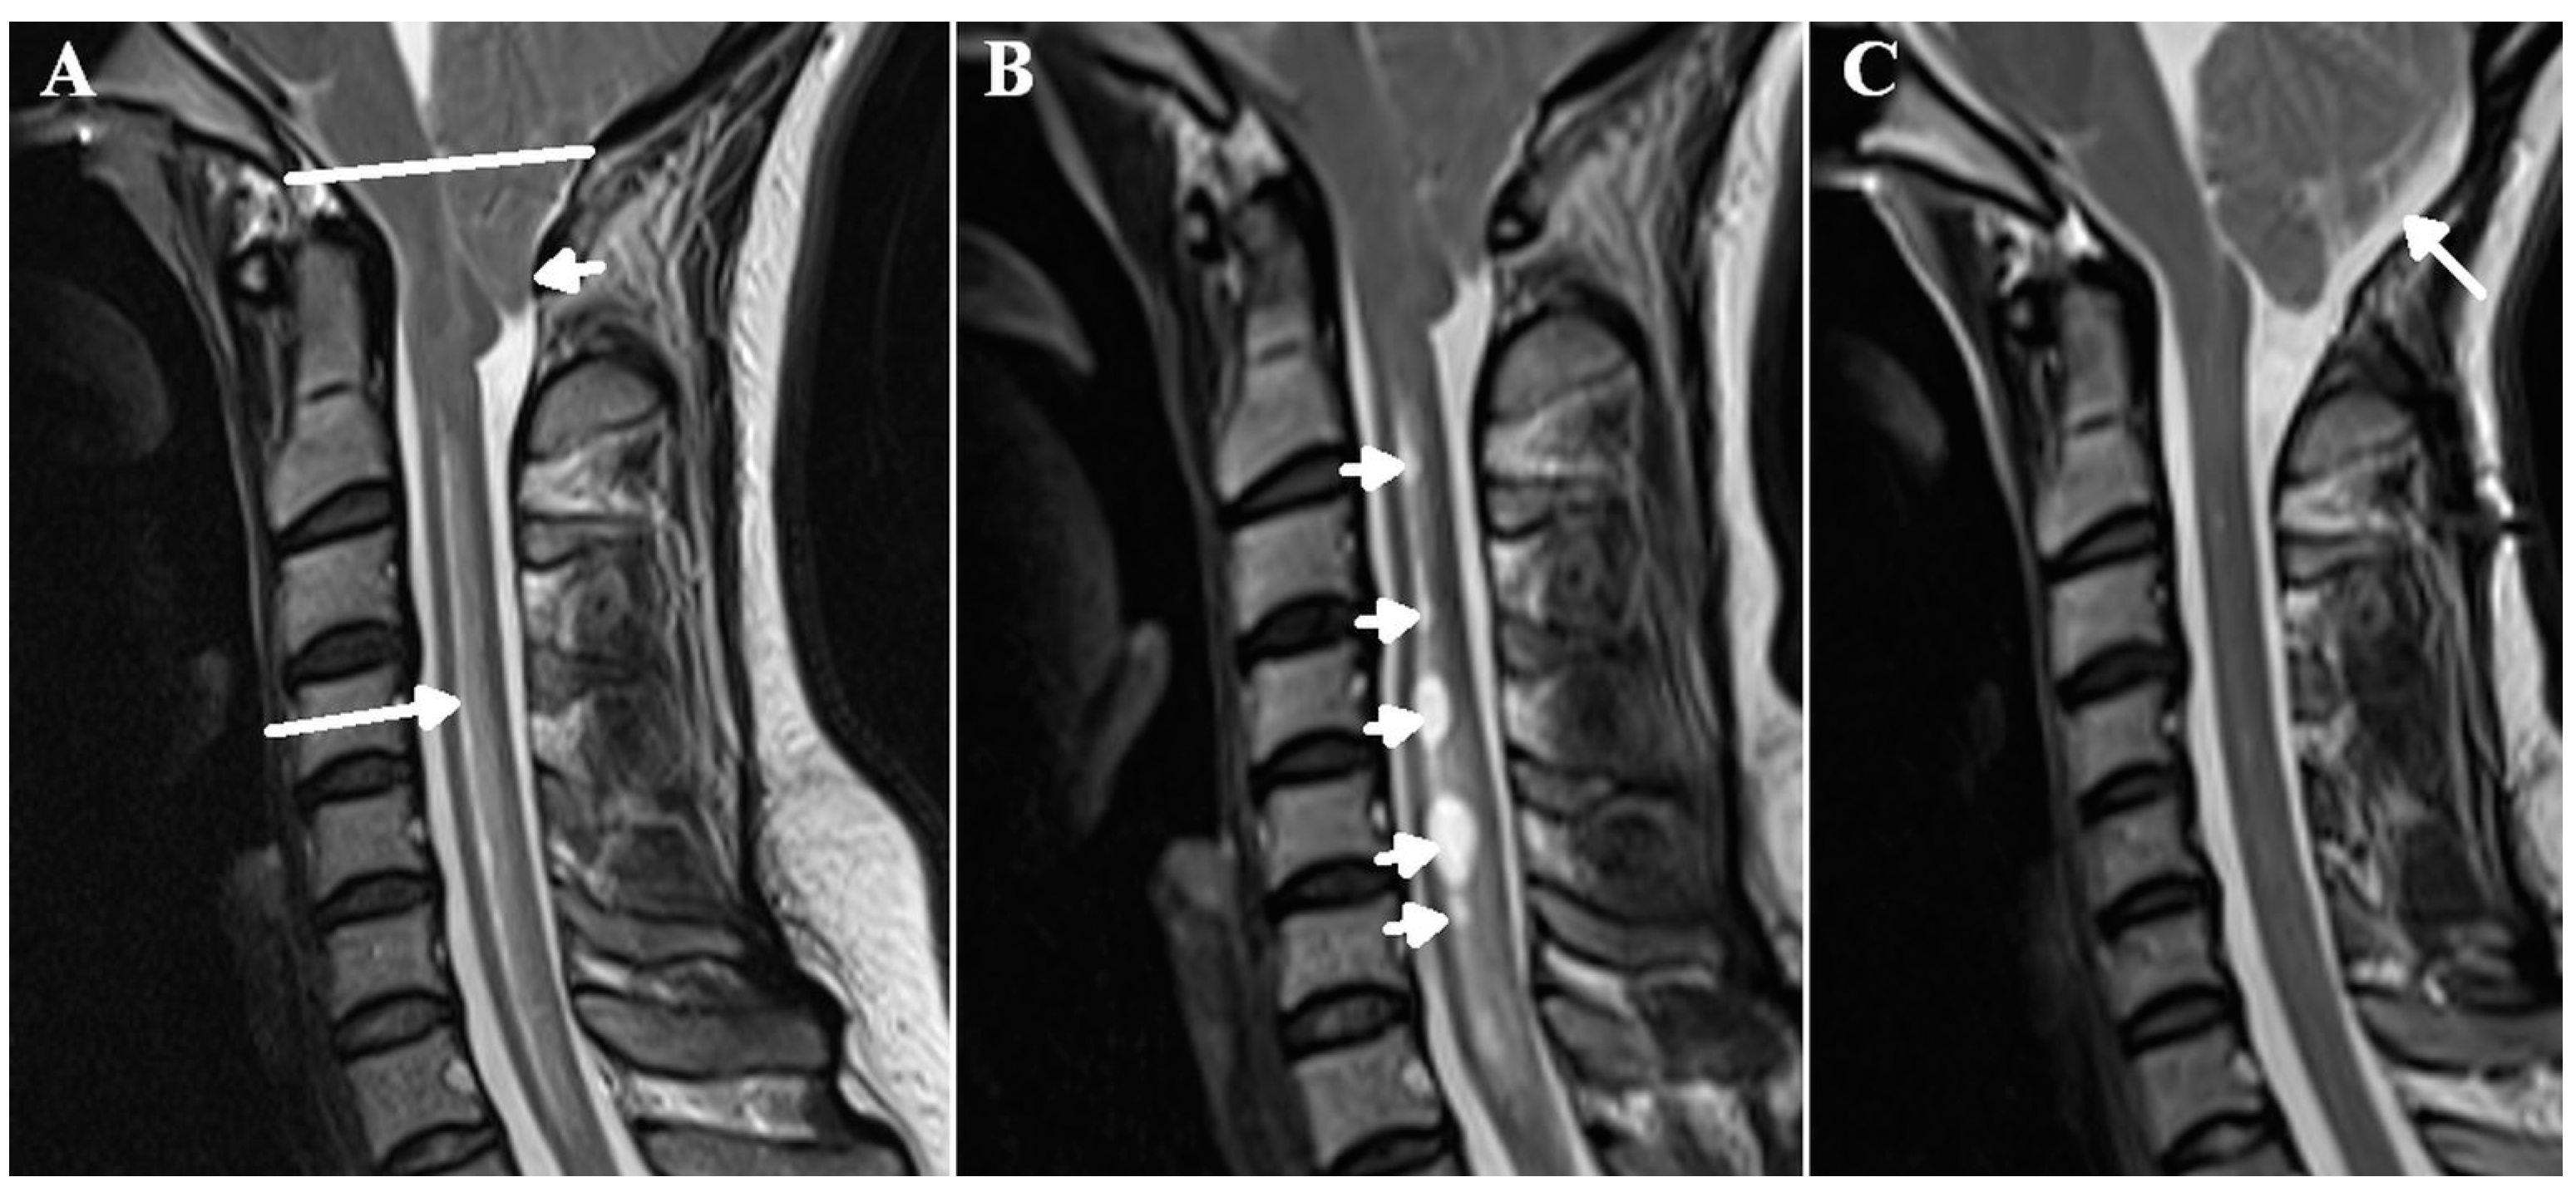

Figure 1.

The progression of edema in syringomyelia. A T2 weighted sagittal MRI of the neck in a 28-year-old female patient who presented with headache on bending and coughing. There is a Chiari 1 malformation with significant cerebellar tonsil herniation (small white arrow) below the foramen magnum (white line) leading to reduced spinal compliance. There is spinal cord edema from C2 to T1 (long arrow) (A). One year later, following conservative management, there were multiple cystic cavities developing (arrows) (B). Following posterior fossa decompression (arrow), there is now improved compliance in the spinal canal with the resolution of the edema and the cystic cavities previously noted (C).

The findings from patients with multiple sclerosis (MS) appear to be similar to those found for patients with hydrocephalus. The cortical veins in MS are 29% larger in cross-section than those in matched controls, suggesting an increase in venous transmural pressure of approximately 6.5 mmHg [15]. In syringomyelia secondary to Chiari 1 malformation, Capel et al. measured the arterial inflow and pulsation stroke volume at the skull base and compared it to the venous outflow from the sagittal and straight sinuses in patients with Chiari 1 malformation with and without syrinx formation [16]. They looked at the percentage of the arterial blood flow returning via the main venous sinuses and acknowledged that a reduced percentage suggested an increase in the blood returning via collateral pathways. They found that a decrease in the mobile compliance afforded via cervical CSF pulsation in patients with syrinxes was significantly associated with an increase in venous collateral flow, i.e., increased venous pressure. The finding of reduced compliance in syringomyelia is not new. Total intracranial compliance was reduced by 20% in one study [17] and by 28% in another in patients with Chiari 1 malformation [18] (see Figure 1A). Successful posterior fossa decompression surgery was associated with a 54%increase in this compliance [18]. In one study, posterior fossa decompression to increase compliance led to a resolution of the syrinx in 81% and a significant improvement in 19% of patients [19] (see Figure 1C). However, local spinal canal compliance is even more severely reduced than total craniospinal compliance in this disorder. In Chiari 1 malformation with syrinx formation, local cervical compliance is reduced by 45% with a 44% increase in CSF pulse pressure [20]. There is a reduction in compliance surrounding the cord in all forms of syringomyelia, not just in those secondary to foramen magnum obstruction, including those secondary to trauma and arachnoid scarring [20]. The cortical veins are too small to directly visualise in humans with modern imaging but in a kaolin-induced dog model of syringomyelia, microangiograms showed evidence of venous engorgement [21]. Laser Doppler flowmetry has shown a significant increase in regional spinal cord blood flow after the decompression of a syrinx [22], suggesting a reduction in blood flow resistance.